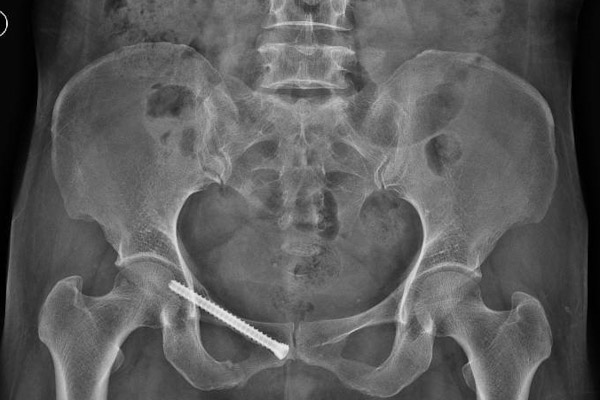

韦阿姨在干活时不慎被推车砸伤,失去了自主行走能力,被家属送入我院创伤骨科,经CT检查,患者为骨盆骨折,需手术治疗。

骨盆位置深,内部脏器结构丰富,血管神经复杂,一旦发生损伤,常常导致相应的血管神经损伤和大出血,所以骨盆骨折手术一直被认为是创伤骨科中最复杂的手术之一。

我院创伤骨科团队根据患者病情进行讨论,最终决定为患者行经皮微创通道螺钉固定术治疗。传统术式需要广泛的软组织剥离,会引起患者术中大量失血及伤口愈合的问题,同时传统大切口可能增加伤口感染的风险。骨盆微创手术不但伤口小,使患者不必再忍受传统手术大切口的痛苦,而且能确保骨折部位的良好复位与维持,牢固固定,为病患术后功能恢复提供了良好的前提保障。

由于骨盆骨折位置深,周边环绕重要的神经和血管,在这么一个完全闭合的空间环境里手术,对医生的技艺和经验要求特别高。施术医生聚精会神,按计划选取进针点,在透视下将螺钉置入约8mm的狭小骨通道中,对骨折部位进行内固定,经过一个小时,手术完美落幕。

经CT检查,结果显示骨折复位良好,骨盆环微创固定后稳定性恢复,在患者体表仅仅留下0.5厘米的小切口。